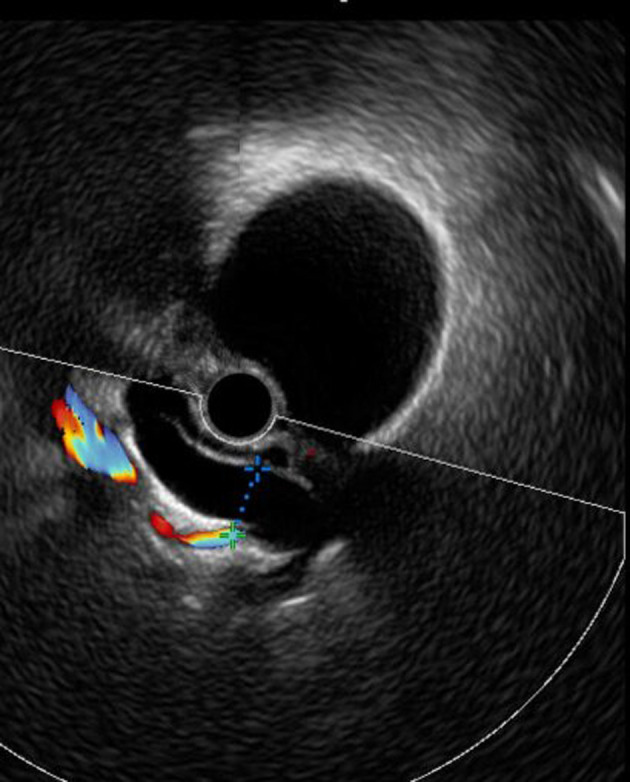

Methods: We conducted an analytical and descriptive retrospective study of 26 patients followed up for acromegaly over 7 years. Biliary complications were screened at diagnosis and follow-up by abdominal ultrasound, biliary magnetic resonance imaging (MRI), and endoscopic ultrasonography (EUS). Data were analyzed using SPSS 21.

Results: The mean age of the patients was 49.6 ± 14 years, with a female predominance (53.8%). The evaluation of biliary complications showed vesicular biliary tract lithiasis and/or sludge in seven patients (29%), including two patients at the time of diagnosis of acromegaly and five patients after an average medical treatment duration of 3 years. Six female patients (24%) had dilation of the bile ducts without the presence of obstruction on biliary MRI and EUS and lithiasis/sludge of the common bile duct, tumor or external compression have been excluded. This condition was discovered incidentally at the diagnosis in five patients and during the follow-up in one patient. The preoperative insulin-like growth factor 1 (IGF-1) levels, disease duration, and female sex were significantly correlated with biliary tract dilation occurrence. Dyslipidemia, the preoperative IGF-1 level, and lanreotide treatment duration were significantly correlated with the occurrence of biliary lithiasis (P < 0.05).